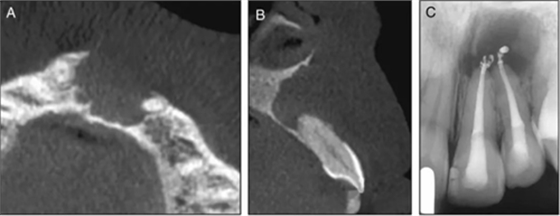

圖3. 術(shù)前CT及根管治療術(shù)后X線片